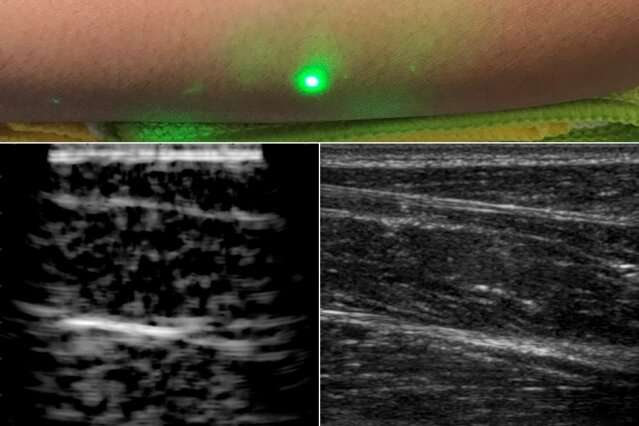

The new laser ultrasound technique leverages an eye- and skin-safe laser system to remotely image the inside of a person.

When trained on a patient’s skin, one laser remotely generates sound waves that bounce through the body, the researchers said.

A second laser remotely detects the reflected waves, which researchers then translate into an image similar to conventional ultrasound.

The researchers scanned the forearms of several volunteers and observed common tissue features such as muscle, fat, and bone, down to about six centimetres below the skin.

These images, comparable to conventional ultrasound, were produced using remote lasers focused on a volunteer from half a metre away.